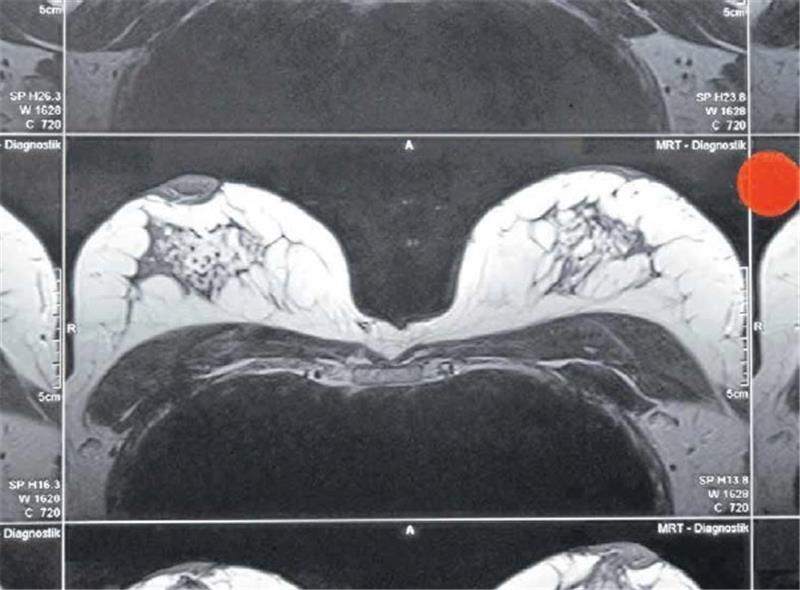

Eine MRT lässt eine genaue Bildgebung der Brust zu, eine generelle Empfehlung für die Untersuchung gibt es aber nicht. Foto: imago stock&people

„Das Mammografie-Screening wird in Braunschweig recht gut angenommen“, sagt Siegmund; auch außerhalb des Vorsorgeangebots wird bereits Frauen ab dem 30. Lebensjahr empfohlen, regelmäßig selbst die Brust abzutasten. Anleitungen dazu gibt es zum Beispiel auf der Webseite der Deutschen Krebsgesellschaft oder bei der Gynäkologin oder dem Gynäkologen. Eine weitere Diagnosemöglichkeit ist eine Brust-MRT, also Magnetresonanztomografie. Im Unterschied zur Mammografie werden dabei keine Röntgenstrahlen eingesetzt; dafür bekommen die Patientinnen ein Kontrastmittel gespritzt. Weil der Tumor stärker durchblutet wird als das umgebende Gewebe, kann sich dort mehr Kontrastmittel anreichern, was ihn auf dem MRT-Bild erkennbar macht, erklärt Siegmund. „Eine MRT machen wir nur nach Indikation“, sagt die Oberärztin; zum Beispiel bei einem unklaren Befund oder um die Rückkehr eines Tumors auszuschließen.